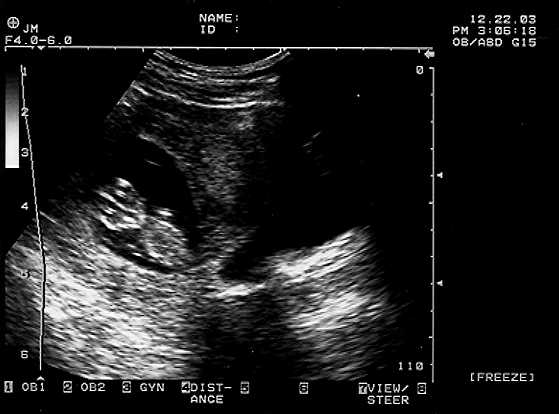

Baby A and Baby B pictures from the December 22 ultrasound are shown here at 11 weeks. Our next ultrasound is February 9, when an ultrasound technician (rather than the doctor) takes a detailed look at all the babies’ vital organs and makes sure they’re both on track. We’re so looking forward to seeing them again – but are ABSOLUTE about keeping their sexes a surprise!